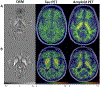

Altered iron metabolism has been hypothesized to be associated with Alzheimer's disease pathology, and prior work has shown associations between iron load and beta amyloid plaques. Quantitative susceptibility mapping (QSM) is a recently popularized MR technique to infer local tissue susceptibility secondary to the presence of iron as well as other minerals. Greater QSM values imply greater iron concentration in tissue. QSM has been used to study relationships between cerebral iron load and established markers of Alzheimer's disease, however relationships remain unclear. In this work we study QSM signal characteristics and associations between susceptibility measured on QSM and established clinical and imaging markers of Alzheimer's disease. The study included 421 participants (234 male, median age 70 years, range 34-97 years) from the Mayo Clinic Study of Aging and Alzheimer's Disease Research Center; 296 (70%) had a diagnosis of cognitively unimpaired, 69 (16%) mild cognitive impairment, and 56 (13%) amnestic dementia. All participants had multi-echo gradient recalled echo imaging, PiB amyloid PET, and Tauvid tau PET. Variance components analysis showed that variation in cortical susceptibility across participants was low. Linear regression models were fit to assess associations with regional susceptibility. Expected increases in susceptibility were found with older age and cognitive impairment in the deep and inferior gray nuclei (pallidum, putamen, substantia nigra, subthalamic nucleus) (betas: 0.0017 to 0.0053 ppm for a 10 year increase in age, p = 0.03 to <0.001; betas: 0.0021 to 0.0058 ppm for a 5 point decrease in Short Test of Mental Status, p = 0.003 to p<0.001). Effect sizes in cortical regions were smaller, and the age associations were generally negative. Higher susceptibility was significantly associated with higher amyloid PET SUVR in the pallidum and putamen (betas: 0.0029 and 0.0012 ppm for a 20% increase in amyloid PET, p = 0.05 and 0.02, respectively), higher tau PET in the basal ganglia with the largest effect size in the pallidum (0.0082 ppm for a 20% increase in tau PET, p<0.001), and with lower cortical gray matter volume in the medial temporal lobe (0.0006 ppm for a 20% decrease in volume, p = 0.03). Overall, these findings suggest that susceptibility in the deep and inferior gray nuclei, particularly the pallidum and putamen, may be a marker of cognitive decline, amyloid deposition, and off-target binding of the tau ligand. Although iron has been demonstrated in amyloid plaques and in association with neurodegeneration, it is of insufficient quantity to be reliably detected in the cortex using this implementation of QSM.

Figures